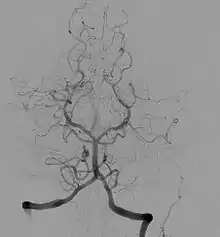

Angiographie cérébrale

Elle est l’application de la méthode de l’angiographie au niveau cérébral. Elle est utilisée en diagnostique et en interventionnelle. Les principales pathologies sont des dilatations des vaisseaux (anévrismes), le rétrécissement de vaisseaux (sténose) ou le blocage.

Elle est utilisée pour diagnostiquer des anomalies sur les vaisseaux sanguins du cerveau ou menant au cerveau (carotides). Ces différentes pathologies vasculaires peuvent être : un blocage (thrombose) ou un rétrécissement (sténose) d’un vaisseau, un anévrisme, une malformation artério-veineuse. On peut réaliser cet examen en préopératoire afin d’observer le système d’irrigation du cerveau. L’angiographie cérébrale permet également de diagnostiquer des pathologies non directement liées au système vasculaire mais ayant une influence sur celui-ci. Elle permet de visualiser des tumeurs, des œdèmes, des hernies, des vasospasmes, l’augmentation de la pression intracrânienne et l’hydrocéphalie.

L’apparition de nouvelles techniques d’imagerie non invasives a réduit l’importance de l’utilisation de l’angiographie cérébrale. On peut citer l’angioscanner, l’échographie doppler, l’angio-imagerie par résonance magnétique. Mais l’angiographie peut être recommandée après un examen précédent, afin d’apporter des informations complémentaires qui ne sont pas visibles par les nouvelles technologies. L’angiographie cérébrale reste l’examen le plus précis dans l’étude de la morphologie des vaisseaux sanguins, ainsi que pour fournir des données dynamiques sur la circulation.